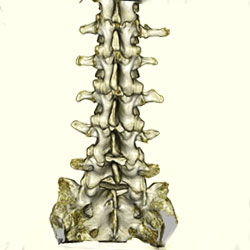

CT

CT